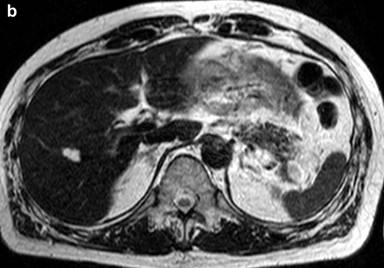

A 53-year-old man was incidentally found to have a cystic tumor in the tail of the pancreas after undergoing an abdominal ultrasound (US), which showed a 41x33 mm cystic mass in the pancreatic tail. He had no abdominal symptoms. The tumor markers, including DUPAN 2, and carbohydrate antigen 19-9, were within the normal ranges. The patient was referred to our hospital for further investigations. A contrast-enhanced CT scan (Figure 1) showed a non-enhanced cyst between the spleen and the pancreas with no solid component. Magnetic resonance cholangiopancreatography (Figure 2) revealed that the main pancreatic duct was regular and had no dilatation, and there was no communication between the cyst and the pancreatic duct. Magnetic resonance imaging (MRI) showed a lesion with a slightly high signal on a T1-weighted image; the lesion, which was well circumscribed, was in the tail of the pancreas (Figure 3). MRI on a T2-weighted image also showed the lesion with a high signal. The cystic tumor was negatively visualized on the PET image. Endoscopic ultrasound (EUS) was performed, which showed a 55x31 mm pancreatic tail lesion with a solid and cystic mixed component (Figure 4a). An endoscopic ultrasound-guided fine-needle aspiration biopsy in a trans-gastric approach of this lesion suggested a diagnosis of a benign squamous cyst (Figure 4b).

Figure 3. Abdominal magnetic resonance imaging findings. a. Slightly high intensity on a T1-weighted image. b. High intensity on a T2-weighted image. |